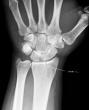

She was walking to work and fell in a pothole.

So now we're in the ER, waiting for X-ray results or maybe some pain meds.